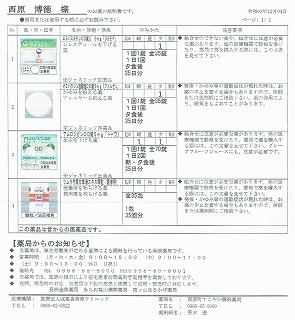

2021.11.13より 西原クリニック 0968-62-0622

2024.4.13 オロパタジンに戻る

2024.3.9 鼻炎と目のかゆみがひどく、オロパタジン⇒デザレックス&点眼薬 アレジオン に変更 2.10 血液検査結果

22.10.29 鼻炎薬吸引 モメタゾン点鼻液50μg 噴霧用 5mg10g 杏林 56噴霧用

22.09.10

2022.02.19